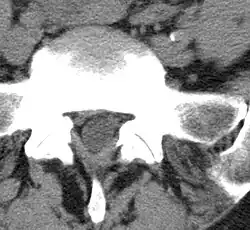

Spondylarthrose im Segment L5/S1 (lumbosakraler Übergang). In dieser CT-Aufnahme ist deutlich zu sehen, wie die degenerativen Veränderungen der Facettengelenke sich in den Spinalkanal vorwölben.

Analog zu arthrotischen Deformierungen an den großen Extremitätengelenken, kommt es zu Verbreiterungen der knöchernen Anteile, einer Sklerosierung (Verdichtung) des unter dem Knorpel gelegenen Knochens, einer Schwellung der Gelenkkapsel (Ergussbildung). Da die aus dem Spinalkanal entspringende Nervenwurzel in unmittelbarer Nähe des Wirbelbogengelenkes verläuft, kann es bei degenerativ verursachten Reizzuständen des Gelenkes zu einer Quetschung oder Irritation der Nervenwurzel kommen. Dadurch kann es zu ausstrahlenden Schmerzen in Form einer Lumboischialgie oder Zervikobrachialgie kommen (siehe: Facettengelenksyndrom).

Mithilfe von Bildgebenden Verfahren, wie Computertomographie oder Magnetresonanztomographie, können degenerative Veränderungen der kleinen Wirbelbogengelenke in Relation zum Spinalkanal bzw. zu den Spinalnerven gut beurteilt werden.